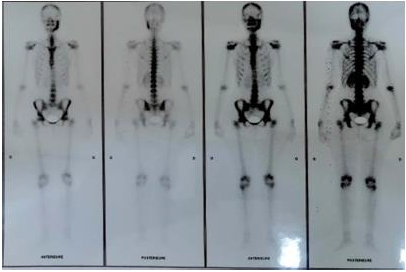

Histological examination predominantly showed chronic inflammatory infiltration and medullary fibrosis. Based on the findings, diagnosis of primary chronic osteomyelitis of the mandible had been made. Complementary scintigraphy was indicated to search any possible extra-oral lesions. No other scintigraphic abnormality of radiotracer fixation on the rest of the osteoarticular system was revealed. Thus, diagnosis of recurrent multifocal osteomyelitis was ruled out (Figure 2). Follow-up was marked with pain, swelling, and mouth opening limitation despite medication including non-steroidal anti-inflammatory drugs: Iboprofen 400mg (twice a day), levofloxacin (Tavanic 500 3 times/day), and paracetamol (Panadol 3g/day). A second surgical intervention was indicated12 months later because of the persistence of symptomatology, especially pain and trismus. The patient underwent decortication of the mandible (the corpus). Pharmaceutical management was based on anti-inflammatory drugs (Iboprofen 500mg), antibiotics: Clindamycin (Dalacine 600mg 2 tab 3 times / day), Levofloxacin (Tavanic 500mg twice a day) and Paracetamol (1g 3 times a day). The patient also received 40 HBO sessions. The patient reported an improvement marked with a decrease in pain and mouth opening restriction despite the persistence of a small and firm swelling of her left mandibular angle and the occasional onset of mild pain that was efficiently relieved with paracetamol. The consultation day, extra-oral examination revealed a firm swelling of the patient’s left jaw extending to the mandibular as well as the temporal areas. Mild pain was present at palpation. The patient had a severe limitation of the mouth opening (1cm). Intra-oral examination revealed a deformation of the corpus in both the vestibular and lingual sides, with gingival fibrosis (Figure 3). Computed tomography showed diffuse sclerosis and an important thickening of the mandibular bone extending to the homolateral condyle. The emergence of the mandibular canal was also involved. Muscular hypertrophy of the masseter muscle and the lateral pterygoidien muscle were evident, too (Figure 4a & 4b). The 3D reconstruction revealed with great precision the extent of the lesion involving the entire left mandible. (Figure 4c). Moreover, periapical radiolucent images were noticeable on the teeth 37 and 36 with evidence of root resorption. Vitality tests on the teeth 36 and 37 were negative.

Figure 2: Bone scintigraphy revealing No other scintigraphy abnormalities of radiotracer fixation on the rest of the osteoarticular system.